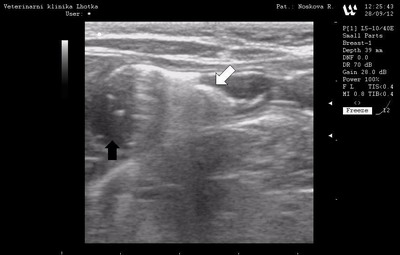

Ultrasonografické vyšetření dutiny břišní, rovněž potvrdilo přítomnost cizího tělesa (bílá šipka) a patologické hromadění tekutiny (černá šipka) ve střevě. Naštěstí vyšetření neobjevilo volnou nitrobřišní tekutinu, která by mohla indikovat perforaci trávícího traktu.

Ultrasonografické vyšetření dutiny břišní Ultrasonografické vyšetření dutiny břišní